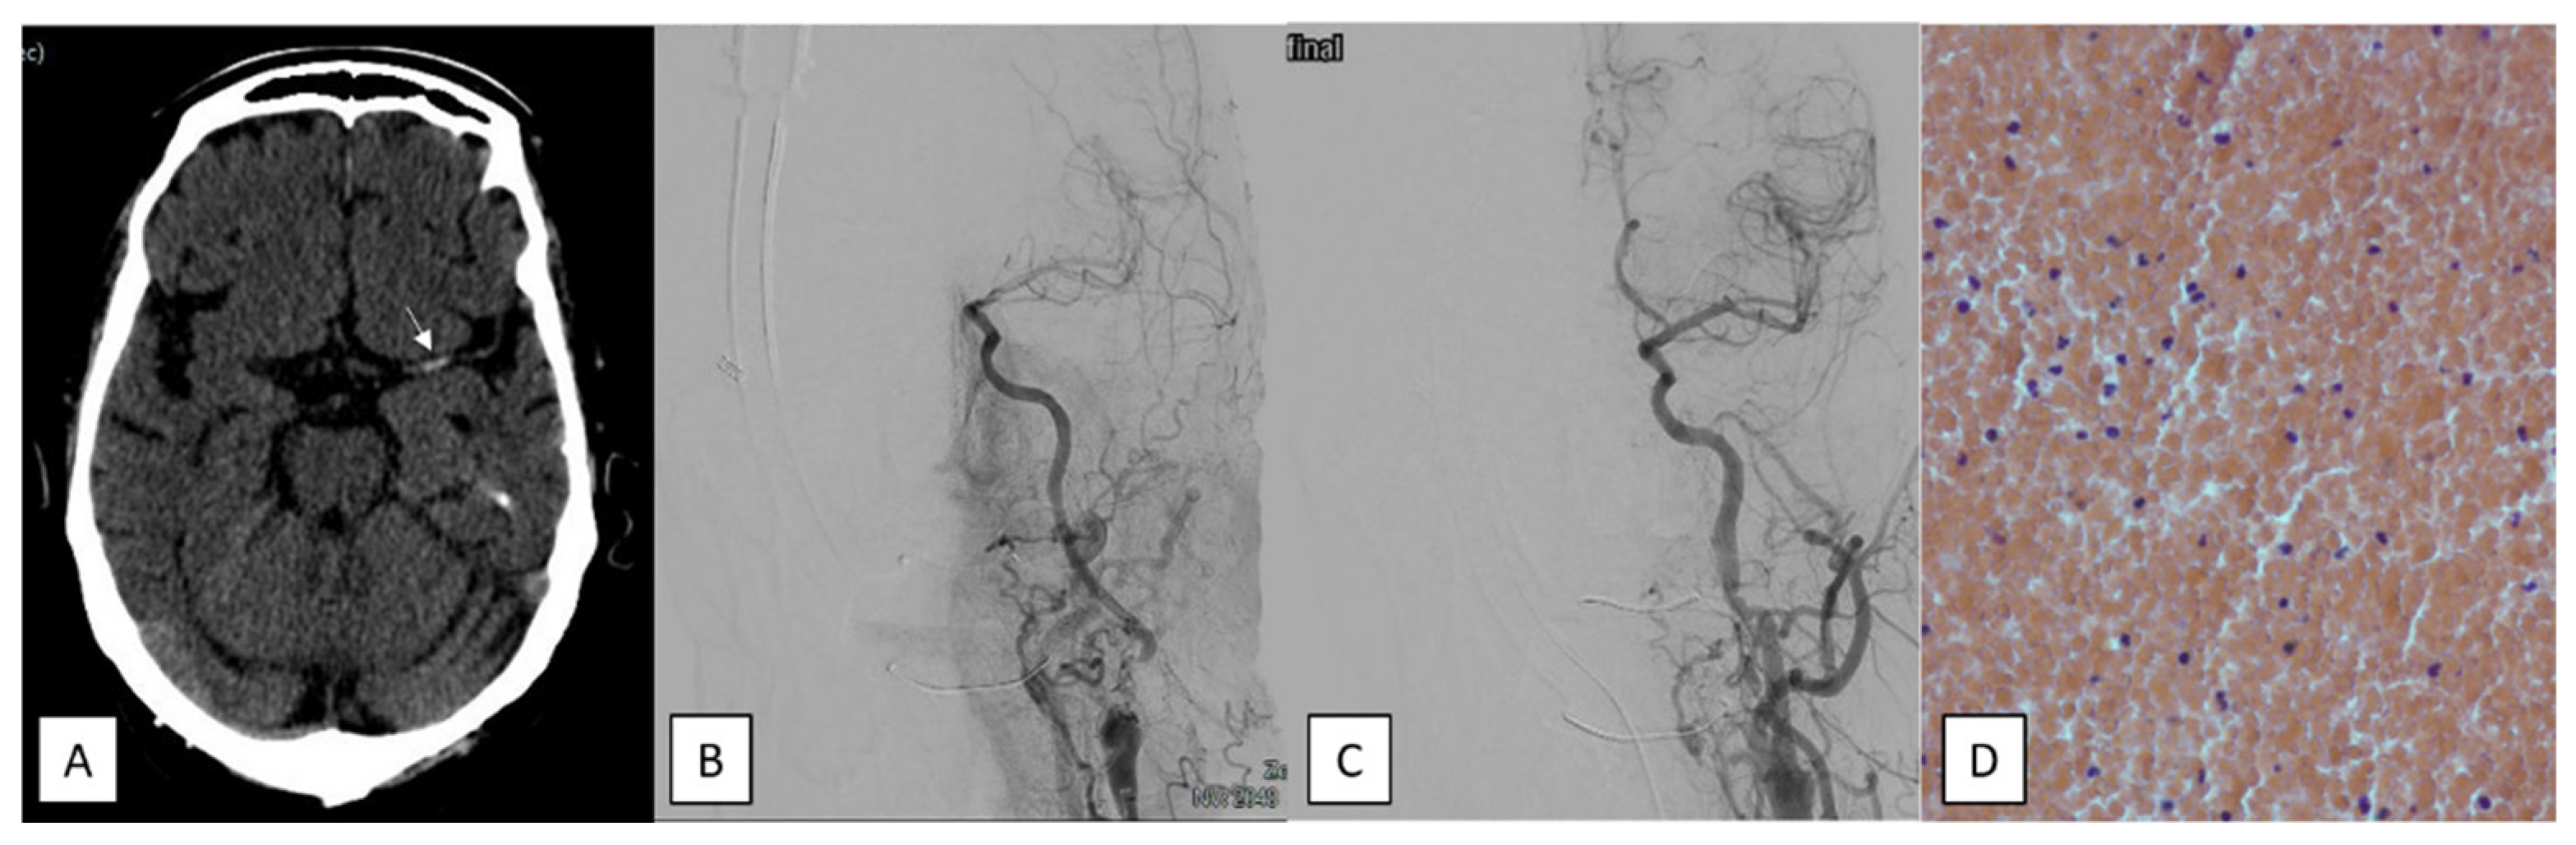

- Clot hardness/burden. A resistance to extraction despite correct device placement and the concomitant existence of a predominant fibrinoplatelet or calcium clot.

- Red, fibrine, and mixed clots: A red clot occurs when the percentage of red blood cells is ≥60%. A fibrin-predominant clot is identified when the ratio of fibrin to platelet is ≥60%. A mixed clot is present if there is no clear predominance of these components.

- Septic clots: These occur when there is an increased number of white blood cells exhibiting morphological alterations. To detect bacteria, the slide was examined at 100× magnification (scale bar, 10 μm) using immersion oil.

- Calcium clots: a major component of calcified tissue.

- Fatty clots: an accumulation of adipose tissue as the major component.